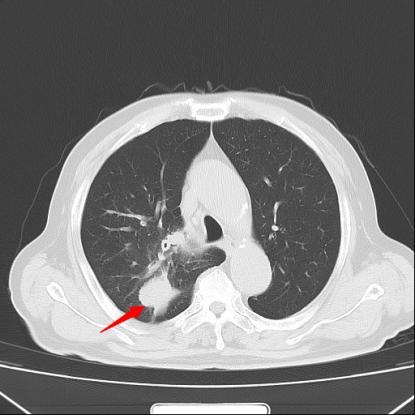

患者王大爷一年前体检发现右肺上叶有一约6×4mm结节,当时未予重视。一年后,他突然出现活动后喘憋症状,复查胸部CT显示右肺上叶后段出现约50×50mm不规则实性团块,影像学高度怀疑肺恶性肿瘤。

经过一个周期的治疗后,患者喘憋、咳嗽等呼吸道症状明显缓解,复查影像显示右肺上叶肿物显著缩小,疗效评估良好。这一结果让患者及家属重拾治疗信心,也为下一阶段治疗奠定了基础。